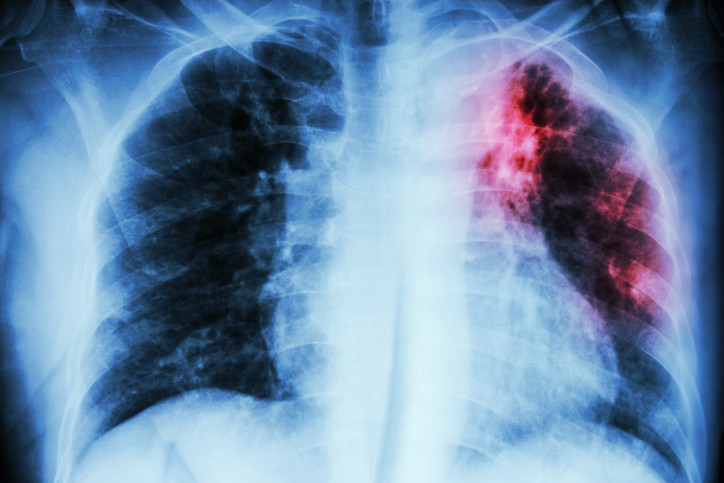

Verem, tüberküloz basili adı verilen bakterinin neden olduğu enfeksiyöz bir hastalıktır. Bu hastalık genellikle yavaş başlar, haftalar hatta aylar içinde ilerler. Aslında zatürenin daha sinsi seyreden bir alt tipi gibi düşünebiliriz. Zamanla akciğerlerde kalıcı hasara yol açarken tedavi edilmediğinde ölümcül sonuçlara sebep olabiliyor.

Uzun süren öksürük, balgamda kan görülmesi ve açıklanamayan kilo kaybının tüberkülozun erken belirtileri olabilir. Bu şikâyetler her zaman kanser anlamına gelmez. Tüberküloz da bu belirtilerle karşımıza çıkabilir. Bu nedenle erken dönemde mutlaka bir uzmana başvurulmalıdır.